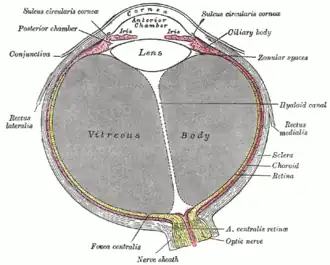

Horizontal section of the eyeball.

Horizontal section of the eyeball. -